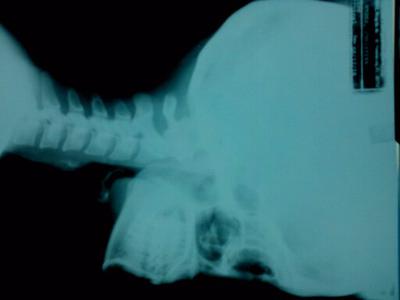

my straight neck

What's good in your case, is that from the x-ray you enclosed the disc spaces appear quite good, though I am unable to see the so called joints of luschka. Their state is vital in the prognosis. Could you attach more pics, or at least send the radiological report.